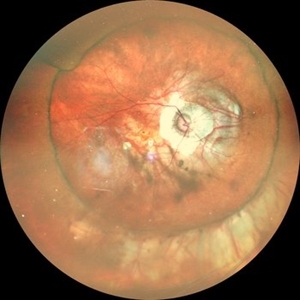

Giant Retinal Tear with Retina Detachment, Both Eyes

Fundus photograph of a 13 year-old female with giant retinal tear and retinal detachment in both eyes.

Photographer: Dr. Akansha Sharma-Retina Foundation, Ahmedabad

Condition/keywords: giant retinal tear, proliferative vitreoretinopathy (PVR)